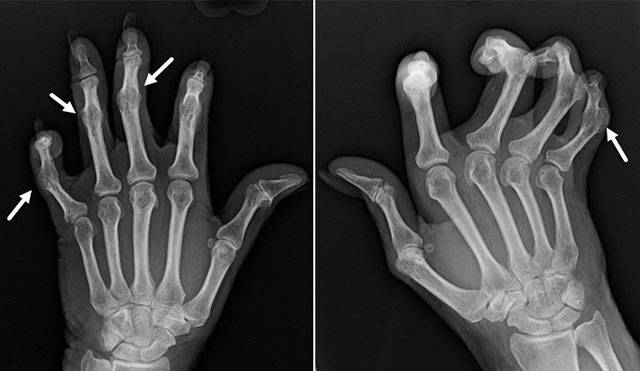

- Характеризуется неподвижностью суставов, которые сильно разрушены. Остеофиты наглядно видны, образуя узелковые наросты: проксимальные (сбоку сустава) – Бушара, дистальные – Гебердена.

Движения кисти ограничены (трудно сгибать, разгибать, сжимать кулак и т. д.), сопровождаются грубым хрустом, блокадами (защемление, обездвиживание из-за попадания кусочка омертвевшей ткани между суставными поверхностями) Боль сохраняется постоянно, не проходит даже в покое и усиливается при нагрузках Суставы заметно деформированы (грибовидные и веретеновидные утолщения пальцев), болезненные на ощупь, время от времени припухают, краснеют, воспаляются (синовит) Появляются гиперподвижность, смещение, подвывихи и вывихи фаланг в боковых направлениях |

Суставы не двигаются (сращение тканей, анкилоз) Болевой синдром сильный, интенсивный Выраженная деформация суставов, искривление пальцев Регулярно повторяется синовит (острая боль, припухлость, воспаление, краснота, температура) В процесс вовлекаются мышцы и связки (слабость, дистрофия) |